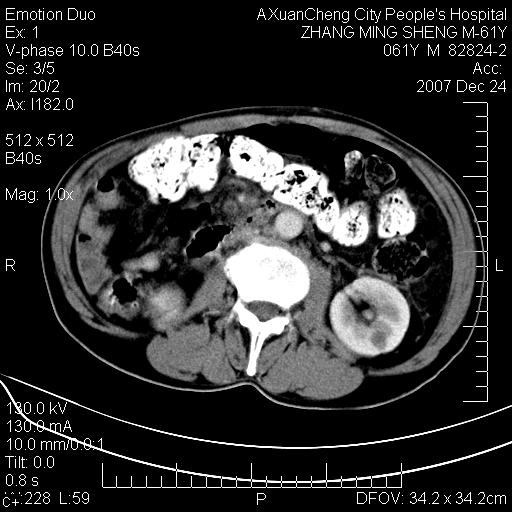

标题: CT11031:M61Y,胰腺占位 [打印本页]

标题: CT11031:M61Y,胰腺占位

大家侃侃门静脉和胆管系统怎么回事,肝内转移?

胰腺癌肝转移

肝硬化,门脉高压,脾肿大;弥漫性肝癌,肝内、门脉、腹膜后淋巴结转移,肝内外胆管扩张,胰头区占位,建议mr检查

胰腺癌伴肝内转移;门脉、肠系膜上v癌栓形成。

考虑为:胰腺癌伴肝脏转移、腹膜后淋巴结转移,门静脉及肠系膜上静脉瘤栓形成。

胰体尾癌伴肝内转移,门静脉及肠系膜上静脉瘤栓形成.

肝硬化,脾大. 胰腺癌伴肝内转移;门脉、肠系膜上v癌栓形成。